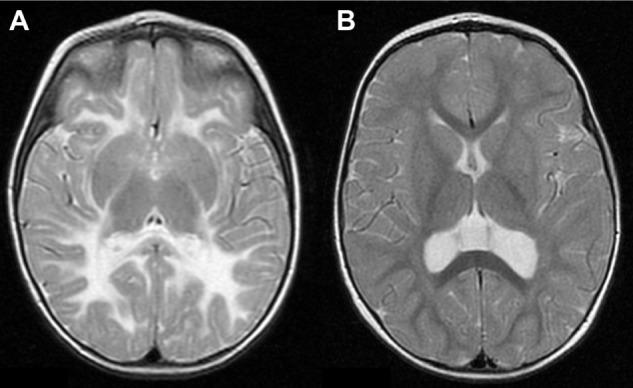

Vanishing white matter (VWM) leukoencephalopathy is one of the most prevalent hereditary white matter diseases. It has been associated with mutations in genes encoding eukaryotic translation initiation factor (eIF2B). We have compiled a list of all the patients diagnosed with VWM in Spain; we found 21 children. The first clinical manifestation in all of them was spasticity, with severe ataxia in six patients, hemiparesis in one child, and dystonic movements in another. They suffered from progressive cognitive deterioration and nine of them had epilepsy too. In four children, we observed optic atrophy and three also had progressive macrocephaly, which is not common in VWM disease. The first two cases were diagnosed before the 1980s. Therefore, they were diagnosed by necropsy studies. The last 16 patients were diagnosed according to genetics: we found mutations in the genes eIF2B5 (13 cases), eIF2B3 (2 cases), and eIF2B4 (1 case). In our report, the second mutation in frequency was c.318A>T; patients with this mutation all followed a slow chronic course, both in homozygous and heterozygous states. Previously, there were no other reports to confirm this fact. We also found some mutations not described in previous reports: c.1090C>T in eIF2B4, c.314A>G in eIF2B5, and c.877C>T in eIF2B5.

消失性白质(VWM)脑病是最常见的遗传性白质疾病之一。它与编码真核生物翻译起始因子(eIF2B)的基因突变有关。我们整理了西班牙所有被诊断为VWM的患者名单;我们找到了21名儿童。他们所有人的首发临床表现都是痉挛,6名患者伴有严重共济失调,1名儿童有偏瘫,另1名有肌张力障碍性运动。他们都有进行性认知衰退,其中9人还患有癫痫。在4名儿童中,我们观察到视神经萎缩,3人还患有进行性巨头症,这在VWM疾病中并不常见。前两例在20世纪80年代之前被诊断。因此,他们是通过尸检研究确诊的。最后16名患者是根据遗传学确诊的:我们在eIF2B5基因中发现了13例突变,在eIF2B3基因中发现了2例突变,在eIF2B4基因中发现了1例突变。在我们的报告中,第二常见的突变是c.318A>T;无论纯合还是杂合状态,携带这种突变的患者病程都很缓慢。此前,没有其他报告证实这一事实。我们还发现了一些之前报告中未描述的突变:eIF2B4基因中的c.1090C>T、eIF2B5基因中的c.314A>G和eIF2B5基因中的c.877C>T。